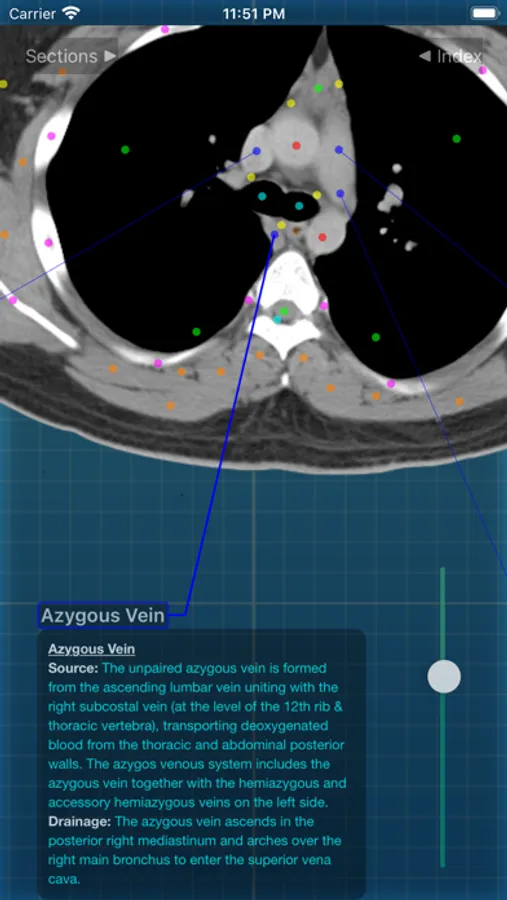

X-Anatomy is a transaxial cross-sectional human anatomy interactive medical imaging atlas using CT images, designed for medical professionals & all students of anatomy.

* Includes hundreds of images from actual human patient body scans.

* Detailed anatomic notes about muscles, vessels, and key anatomic structures

* Complete color-coded index of anatomic structures

* FOLLOW the positions and pathways of your selected anatomic structures automatically as you SCROLL through the image slices.

INCLUDED body section modules cover the major body sections from head to pelvis: CT Brain, CT Neck, CT Sinuses, CT Chest, CT Lungs, CT Abdomen & Male Pelvis, CT Abdomen & Female Pelvis.